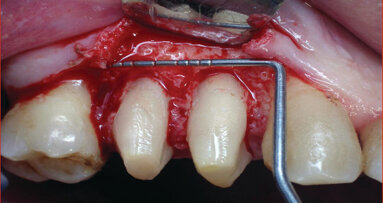

Laser gingivectomy

Gingivectomy was performed by Er:YAG laser (LiteTouch™, by Syneron Dental Lasers, Israel) at the following settings: 200 mJ, 18 Hz, 3-4 water spray level. External bevel gingivectomy with tip (0.4 x 17 mm) was performed. Only 10% Lidocaine spray was used for local anaesthesia. An excisional biopsy was taken during gingivectomy, which was fixed in 10% formalin solution and referred for pathological examination (Fig. 15). The level of pain and discomfort during the treatment and healing period was assessed by visual analog scale (VAS).

The Er:YAG laser ablated the soft tissue easily and effectively and the procedure was performed with local anaesthesia only. Although the Er:YAG laser does not possess good haemostatic action, there was no excessive bleeding during and after the gingivectomy. Healing and the patients’ subjective assessment were estimated one day, one week and one month after the procedures. The healing process proceeded without complications and side effects. Patients reported score 0 in the VAS examination, which meant absence of pain and discomfort during and after the laser gingivectomy procedure. Pathological examination confirmed the diagnosis gingival hyperplasia. The tissue samples showed no thermal damage in the incision area. Wound healing was fast and complete within one to two weeks. There were no side effects or complications. Patients were monitored for recurrence during a one-year period.